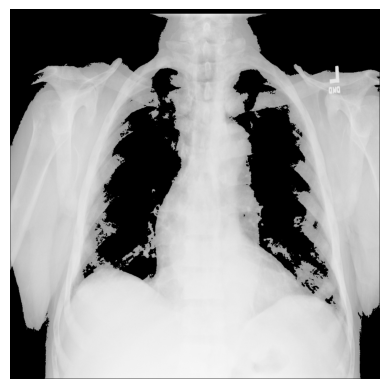

3. Import matplotlib and display the image in a grayscale colormap:

import matplotlib.pyplot as plt

plt.imshow(xray_image, cmap="gray")

plt.axis("off")

plt.show()